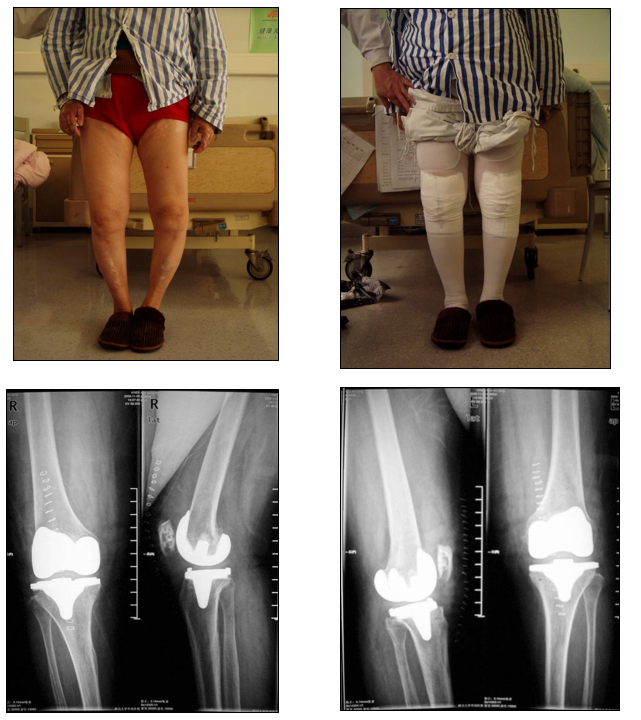

关键三、矫正膝关节外畸形

病因源自股骨,外侧髁的远端和后侧发育不良

股骨远端截骨角度≤5°

屈曲位时内侧松弛外侧紧张

确定股骨外旋、适当松解外侧副韧带

伸直位时内侧松弛

行内侧结构的紧缩或外侧结构的松解

术前确定切骨线,胫骨上端切骨线为0°。外侧平台尽量切薄,而内侧平台则切骨很厚。

下肢残留外翻畸形